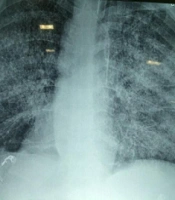

Three days after discharge, the patient was readmitted to the hospital due to persistent epigastric pain and emesis. Treatment with ganciclovir, teicoplanin, and meropenem was started empirically. The following day, the patient developed a dry cough and respiratory distress. A chest X-ray showed diffuse interstitial infiltrates (Figure 1).